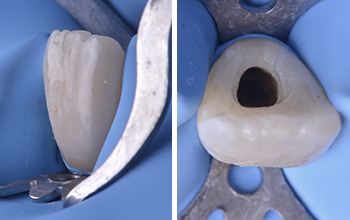

Après mise en place du champ opératoire la cavité d’accès est réalisée. Cette dernière de taille légèrement plus importante qu’une cavité standard doit s’adapter à la situation clinique et à la nécessité de pouvoir réaliser avec précision le bouchon apical.

Fig. 03 et 04 : isolation unitaire à l’aide d’un crampon incisif et vue clinique de la cavité d’accès.